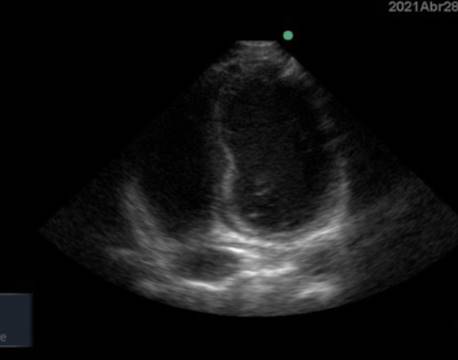

Ecocardiograma Doppler: se observa a nivel de pericardio posterior aumento de refringencia, área de hipomotilidad en el septo apical y pequeño derrame pericárdico. FEVI conservada. Arterias coronarias normales (Figura 1).